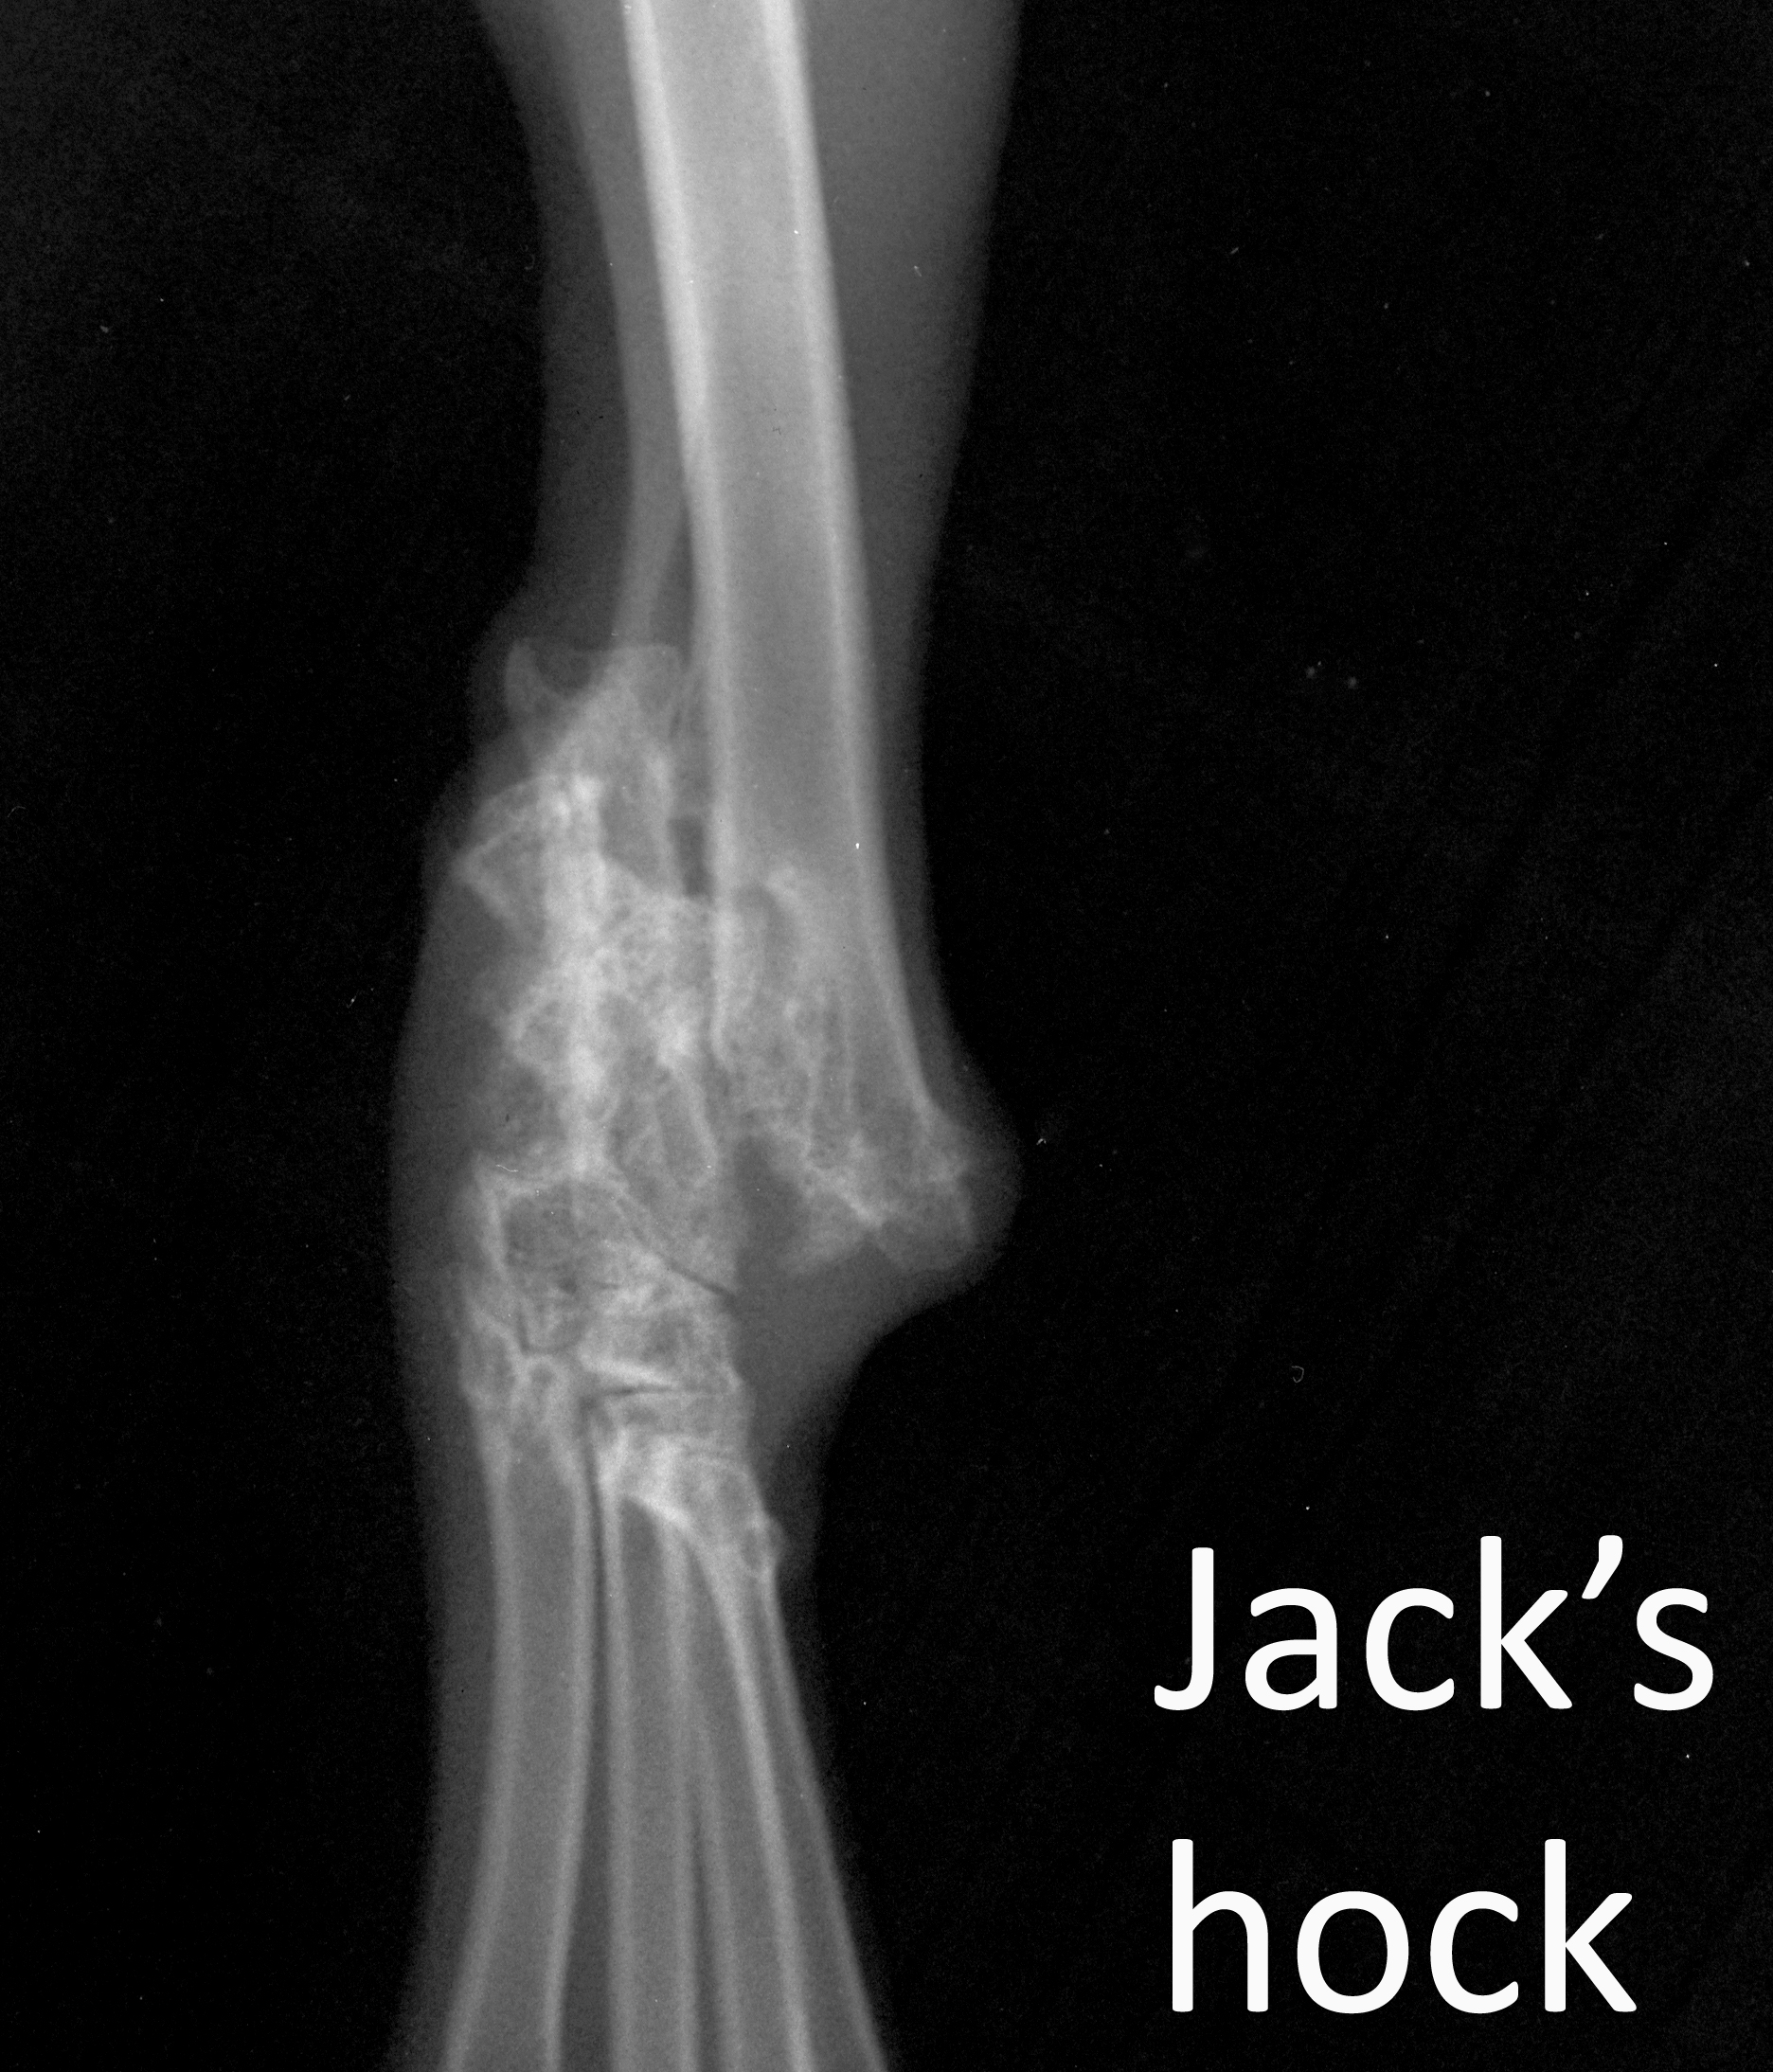

Labelled image of Jack's hock VD